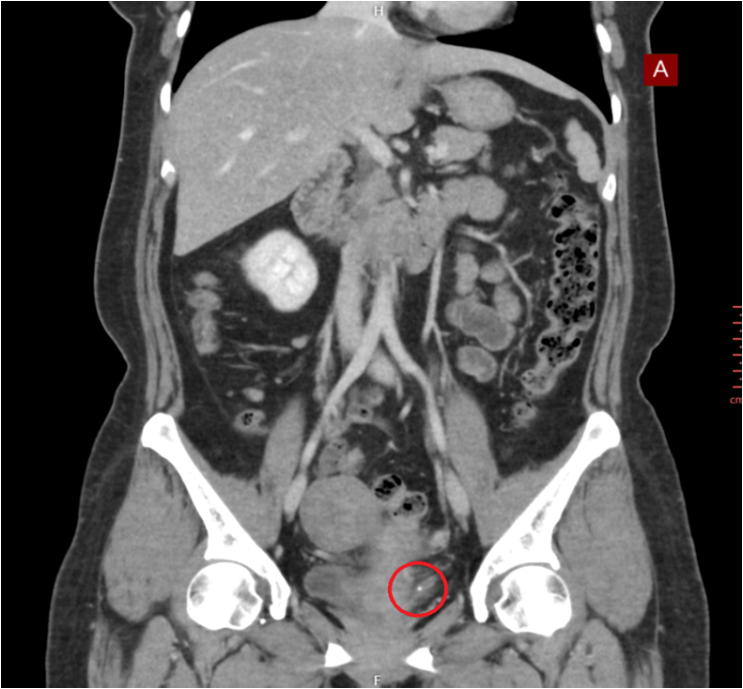

• 복부CT: 좌측 요로 결석 소견 복부CT: 좌측 요로 결석 소견

본원에서 시행한 CT상 좌측 요로 결석이 확인되어 비뇨기과로 전원하였습니다.